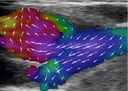

Danish researchers build world's most powerful ultrasound scanner

After seven year of intense research Danish researchers at DTU have build the most powerful ultrasound scanner in the world